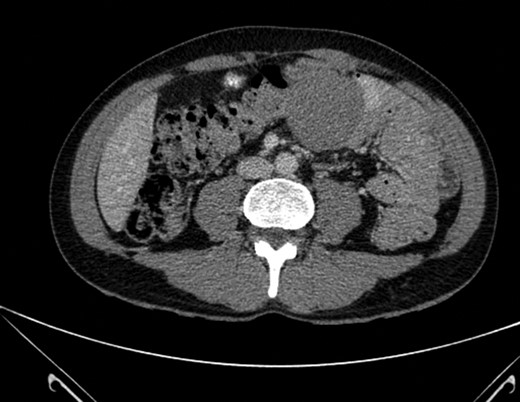

Mr X underwent an esophagogastroduodenoscopy which did not identify any mass or abnormality. He later received a CT abdomen which displayed a well circumscribed 5.5 cm × 5.5 cm × 5.6 cm mass projecting from the mesenteric fat and lying adjacent to the transverse colon with no identifiable cleavage plane between them (Fig. 1). There were no pathologically enlarged lymph nodes identified. Mr X subsequently underwent colonoscopy which was normal.

Well-circumscribed mass measuring 5.5 × 5.6 cm2 projecting from the mesenteric fat and lying adjacent to the transverse colon with no identifiable cleavage plane between them. No pathological lymphadenopathy identified.